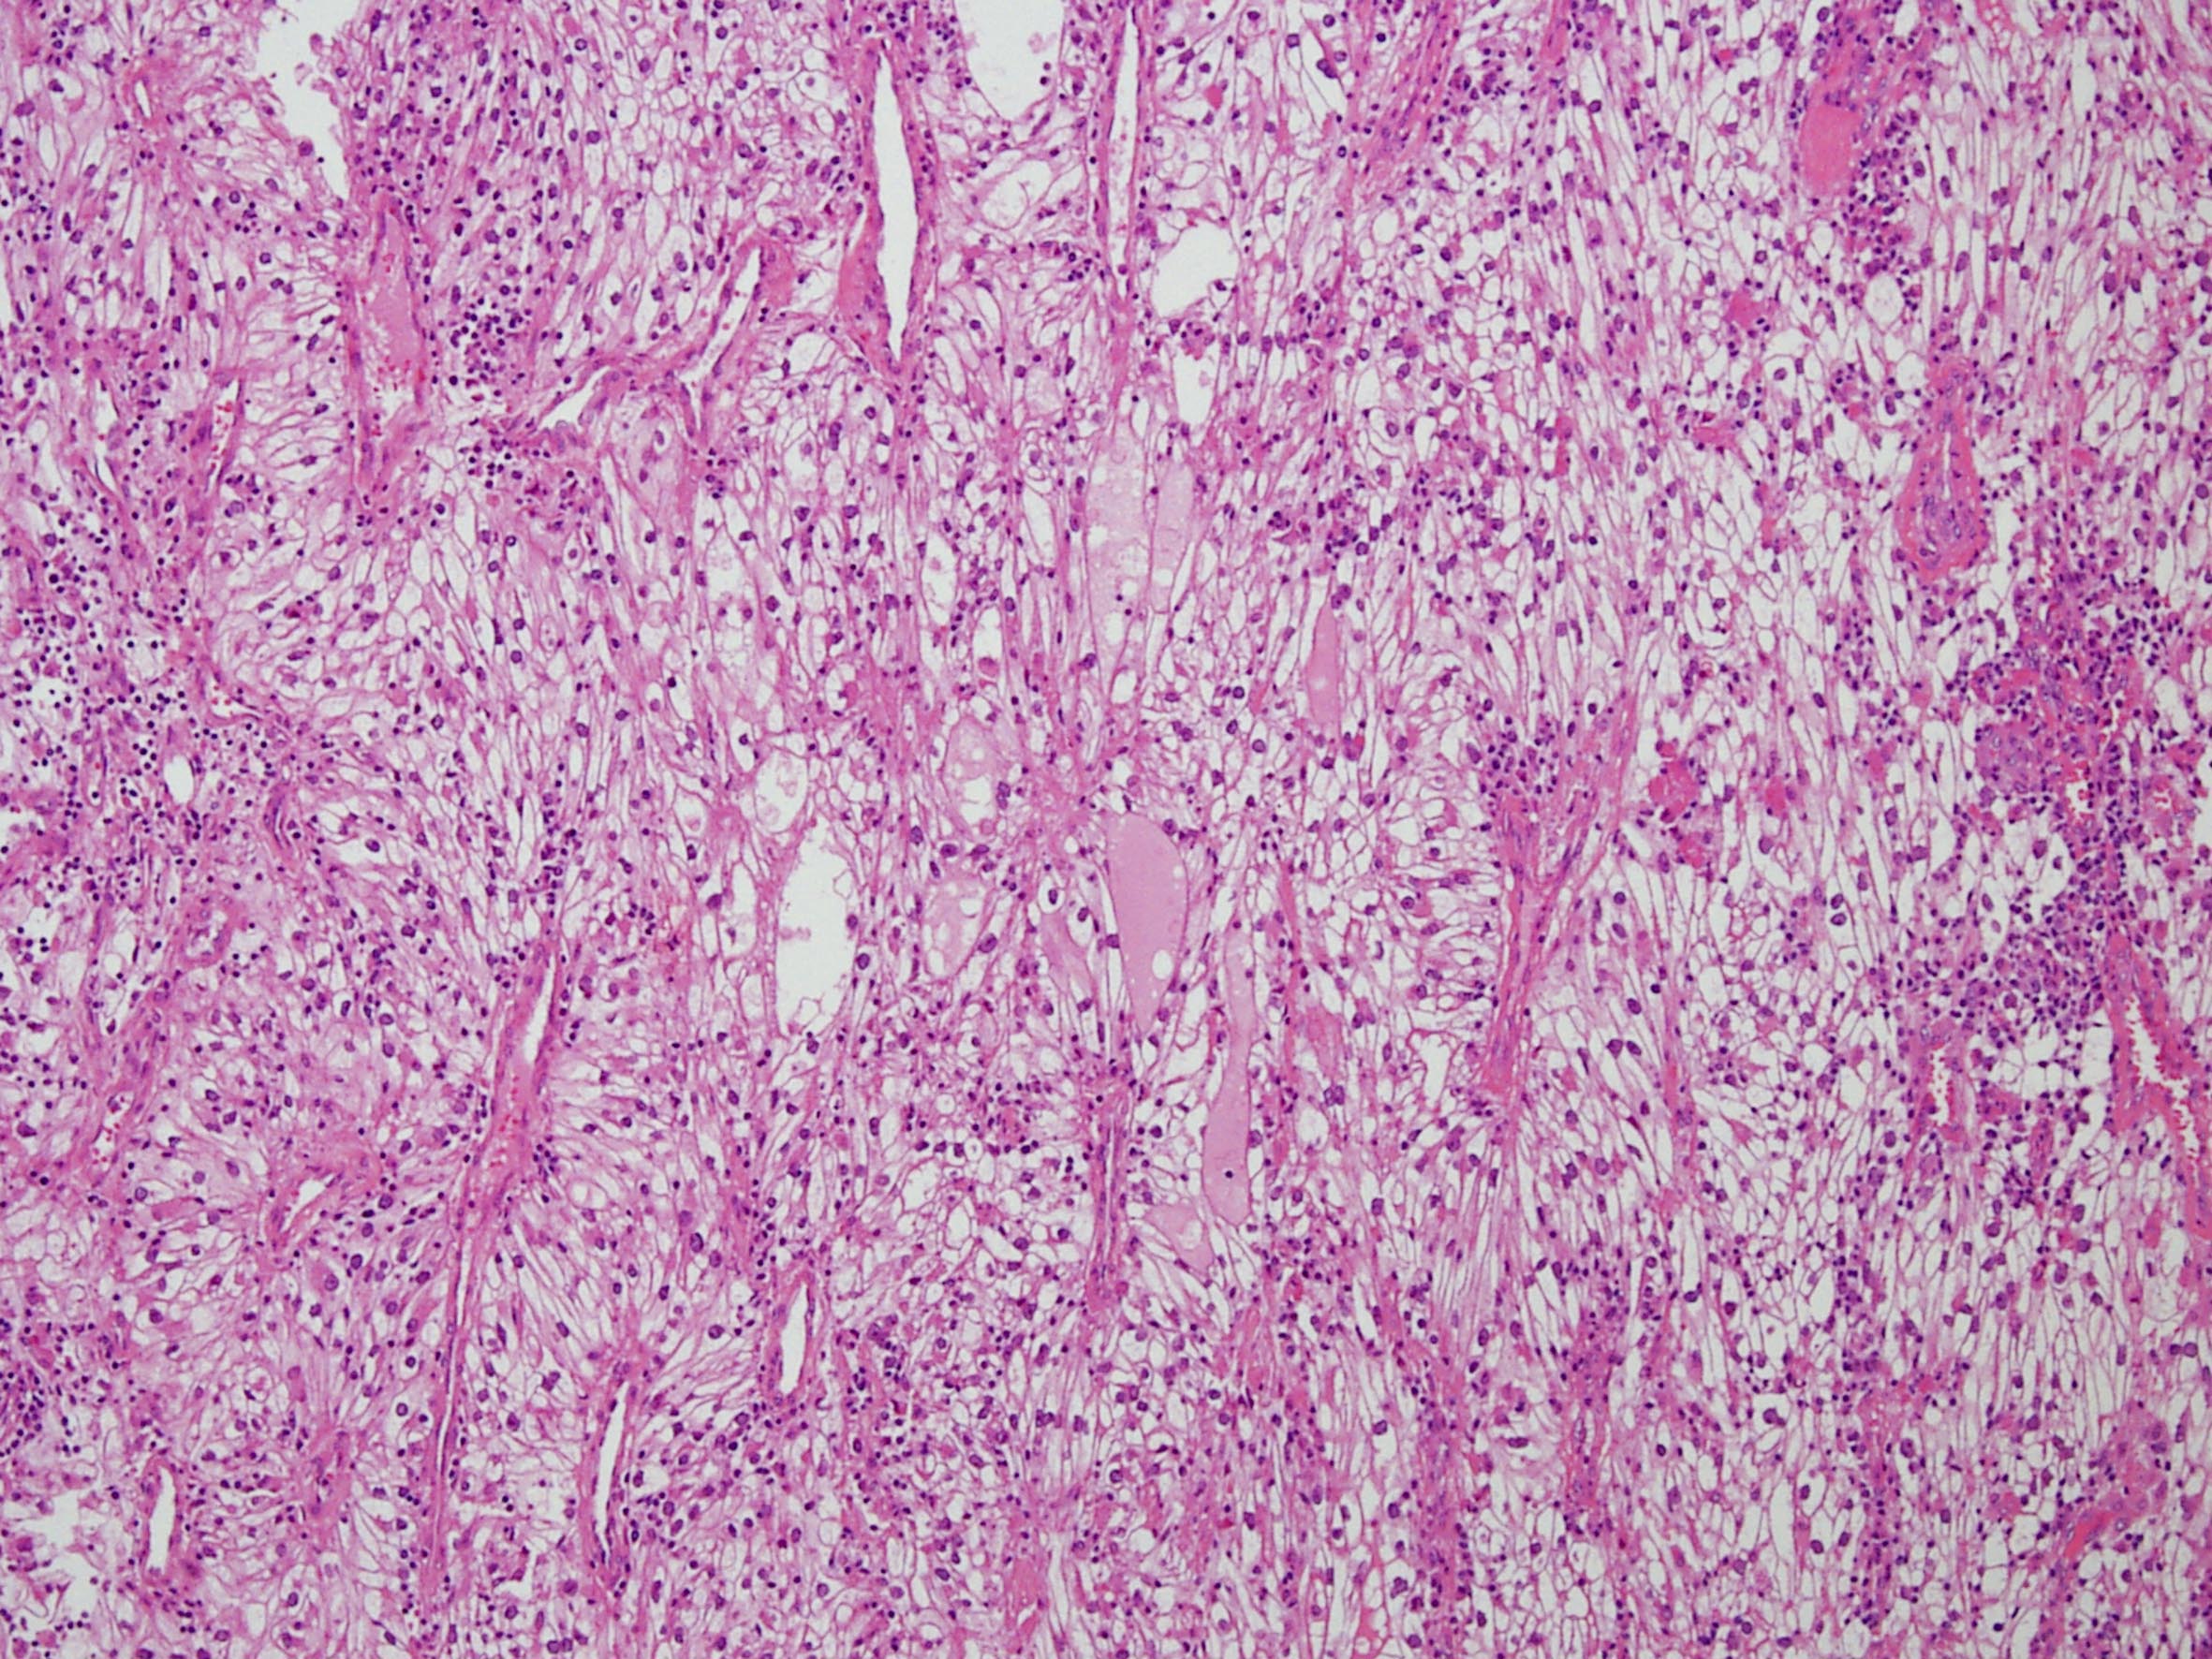

Classification of renal tumors

Case ID: 258